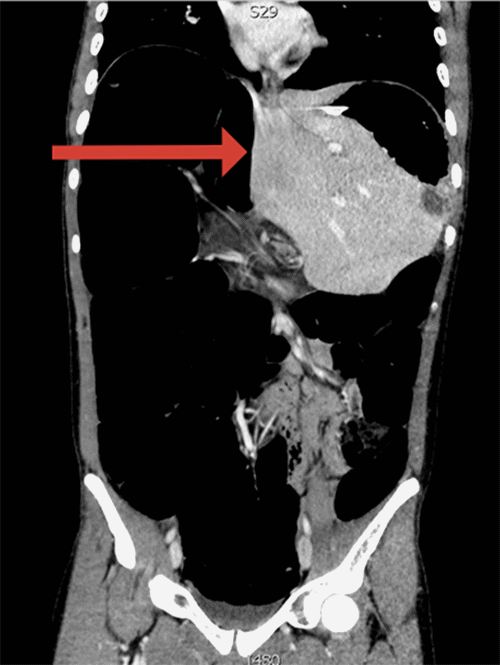

The patient presented with three days of abdominal pain and distention with nausea. He denied any past medical or surgical history. He experienced similar painful episodes over the preceding year that resolved spontaneously within 48 hours. On exam, his abdomen was distended with mild tenderness; rectal exam was normal. CT scan showed a distended esophagus, decompressed small bowel, dilated large bowel, and a significantly medialized liver (Figure 1). As the entire colon was enlarged, colonoscopy was performed to rule out an anatomic cause for large bowel obstruction at the rectosigmoid junction. The patient was found to have a grossly distended colon without obstructing lesions or clear transition point consistent with volvulus. Proximal to the sigmoid colon, there were multiple redundant colonic loops that impeded navigation but were ultimately traversed with difficulty (Figure 2). A rectal decompression tube was placed. Given the nondefinitive findings of the colonoscopy, symptomatic improvement of the patient with decompression, and the patient's young age, additional diagnostic workup was performed for a presumed motility disorder. A full thickness excisional rectal biopsy was obtained for evaluation of Hirschsprung disease.

Figure 1. Coronal CT Scan on Initial Presentation. Published with Permission

Dilated colon with medial displacement of the liver